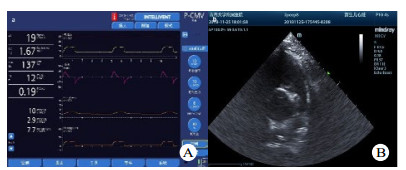

造模前后FAC、SV基线水平时差异均有统计学意义(P < 0.05),提示是ARDS本身造成的影响。PEEP递增时,造模后的SV、TAPSE低于造模前,差异有统计学意义(P < 0.05)。PEEP递增时,造模后TAPSE、SV先增大后减小,差异有统计学意义(P < 0.05)。其中SV分别在PEEP =4 cmH2O及10 cmH2O时最大;TASPE变化反复波动,见表 2。如图 2所示,造模后SV和Cstat随PEEP增加其变化趋势比较,SV和Cstat呈现同向变化关系。

| A、B中细白线勾勒图形为右室切面内腔面积大小比较,与A图比较,B图右心室腔显著扩张 图 3 造模前后犬心脏心尖四腔心超声切面 Fig 3 Comparison of echocardiography before and after modeling |